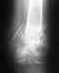

снимок 8/05/10, была на консультации в апреле по адресу Банковский,7, рекомендовали обратиться через 2 месяца ( скорее всего третья операция) , есть сомнения, исход третьей операции будет положительным.